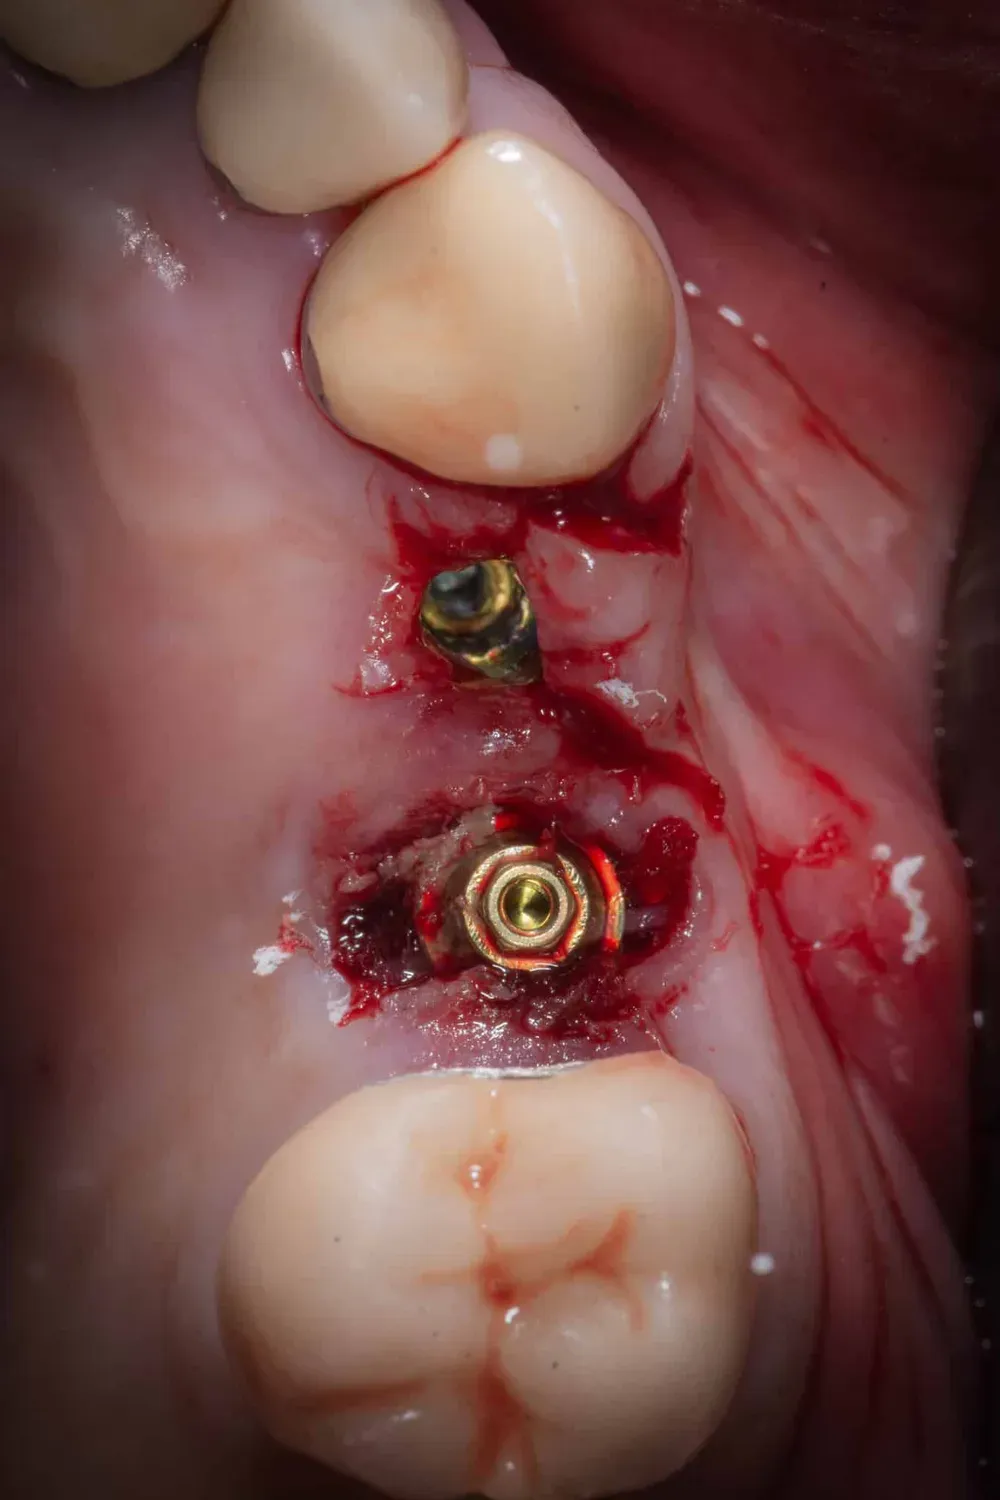

La foto che segue mostra gli impianti in posizione prima della connessione dei monconi protesici (sempre conici). La stabilità di entrambi era superiore ai 50Ncm.

Immagine occlusale immediatamente dopo l

Immagine occlusale immediatamente dopo l’inserimento degli impianti